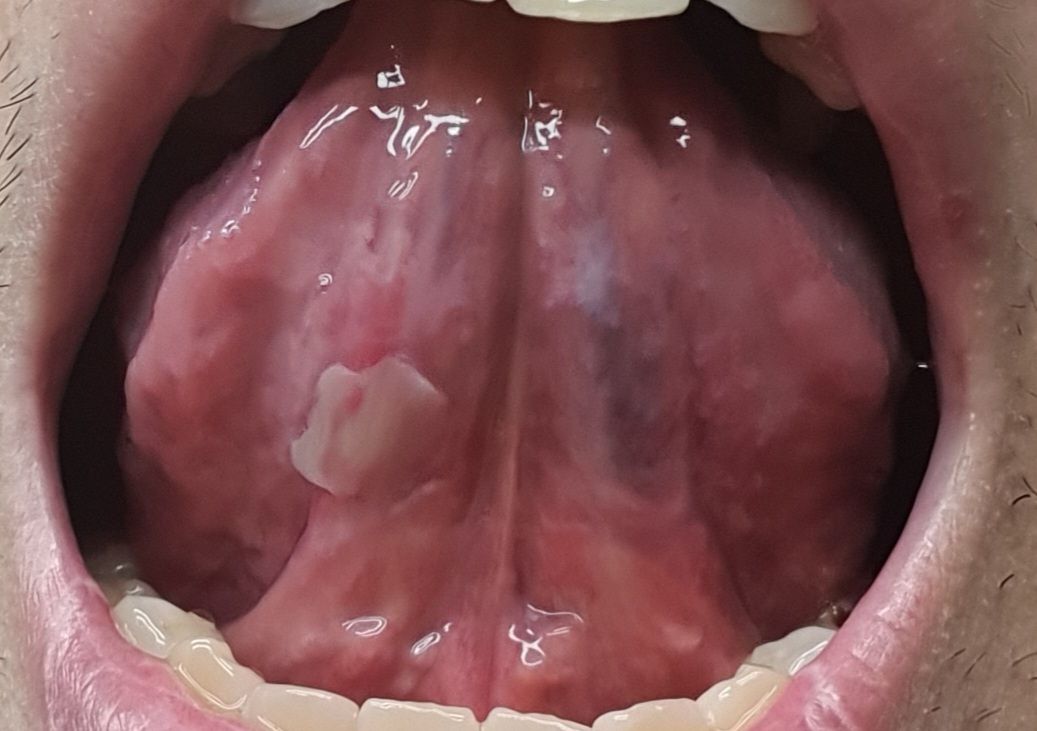

혀 안에 하얀게 났는데 혹시 암인가요?

혀 안에 하얀게 났는데 혹시 암인가요? 일반 구내염이랑 좀 달라보이네요..

통증은 건들면 약간있습니다. 구내염처럼 심한 통증은 아니고 만져보면 막처럼 약간.들리는거 같네요

혀 하방에 구내염처럼 생긴거 같습니다. 치과에 가셔서 소독을 한번 받아보시는게 좋을것같습니다.

연조직에 지속적인 자극이 가해지게 되면 사진처럼 보일 수 있습니다. 해당 부위를 자극하지 않는 것이 좋으며 보통 일 주일 이내에 없어지지만 그 이상 지속된다면 치과에서 진료를 받아보는 것이 좋습니다.

현재 사진상 암일 가능성은 낮으며, 현재 구강 점막에 염증으로 점막이 다소 떨어진 것으로 보입니다. 우선 소독용 헥사메딘 가글액으로 가글하여 관리를 하고, 병변이 2주이상 지속시에는 치과나 이비인후과 진료를 받길 권합니다.

필요 시 조직검사(생검)을 통해 암인지 확인할 수 있습니다.